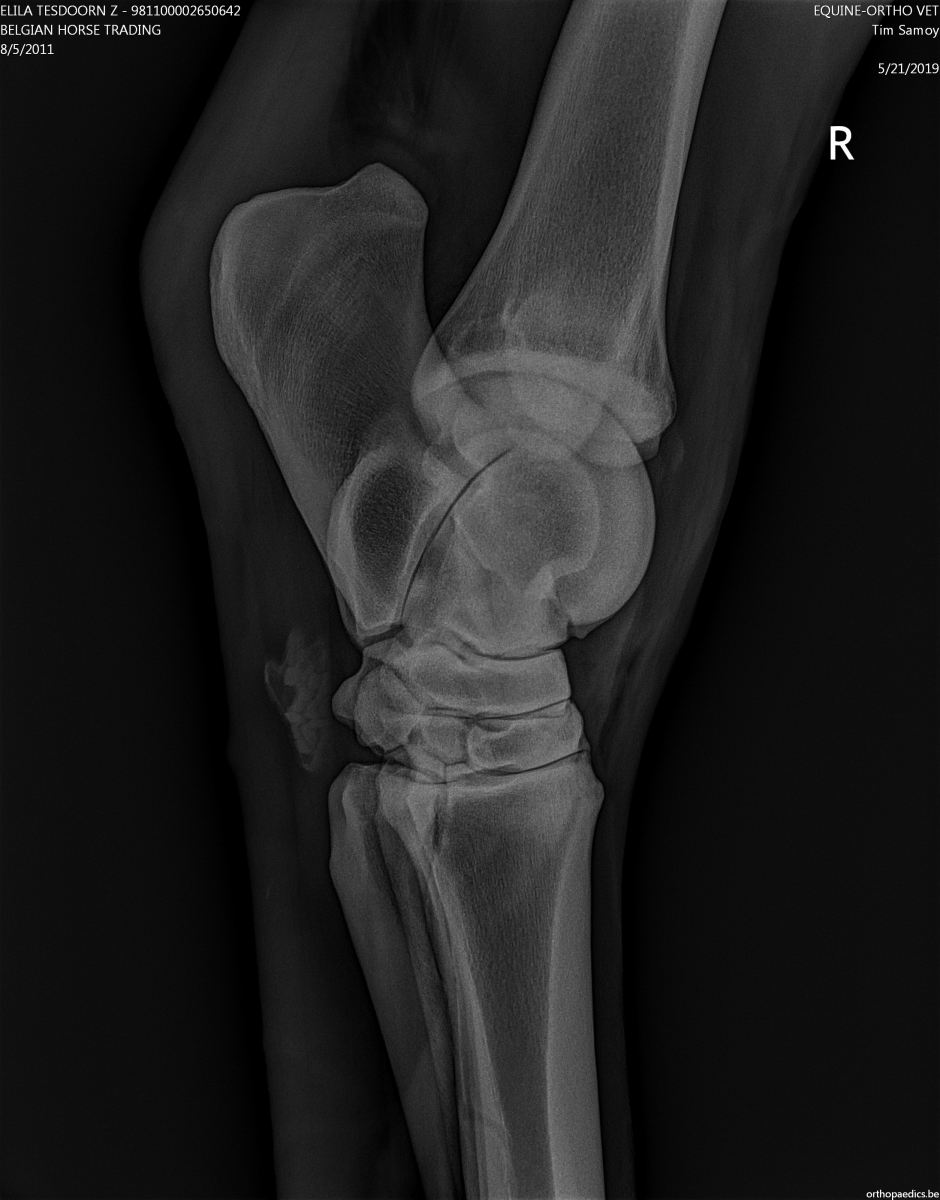

Это кто вам сказал? Если, конечно, рентгену сто лет, то наверное, а на современных машинах видны все прожилки, рельеф, сухожилия и связки как на картинке

Врач, умеющий читать снимки всё увидит.

Вот картинка для иллюстрации. Здесь должно быть виднее. (надеюсь, владелец снимка не против будет, есличе уберу)

Оба сгибателя и межкостник хорошо видны.